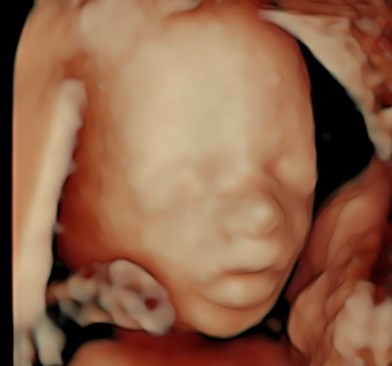

L’ecografia morfologica, come tutte le ecografie ostetriche, deve dare ampio spazio anche ai genitori, alle loro curiosità, al loro bisogno di essere rassicurati, ed è da questa settimana che si possono fare delle bellissime foto in 2D e 3D del volto del piccolo, sia frontalmente che di profilo, innescando invariabili conflitti sulle presunte somiglianze. Se non abbiamo eseguito l’ecografia pre-morfologica, è questo il momento in cui finalmente abbiamo la conferma se il piccolo è une “tesorino” (sinistra) oppure una “tesorina” (destra).